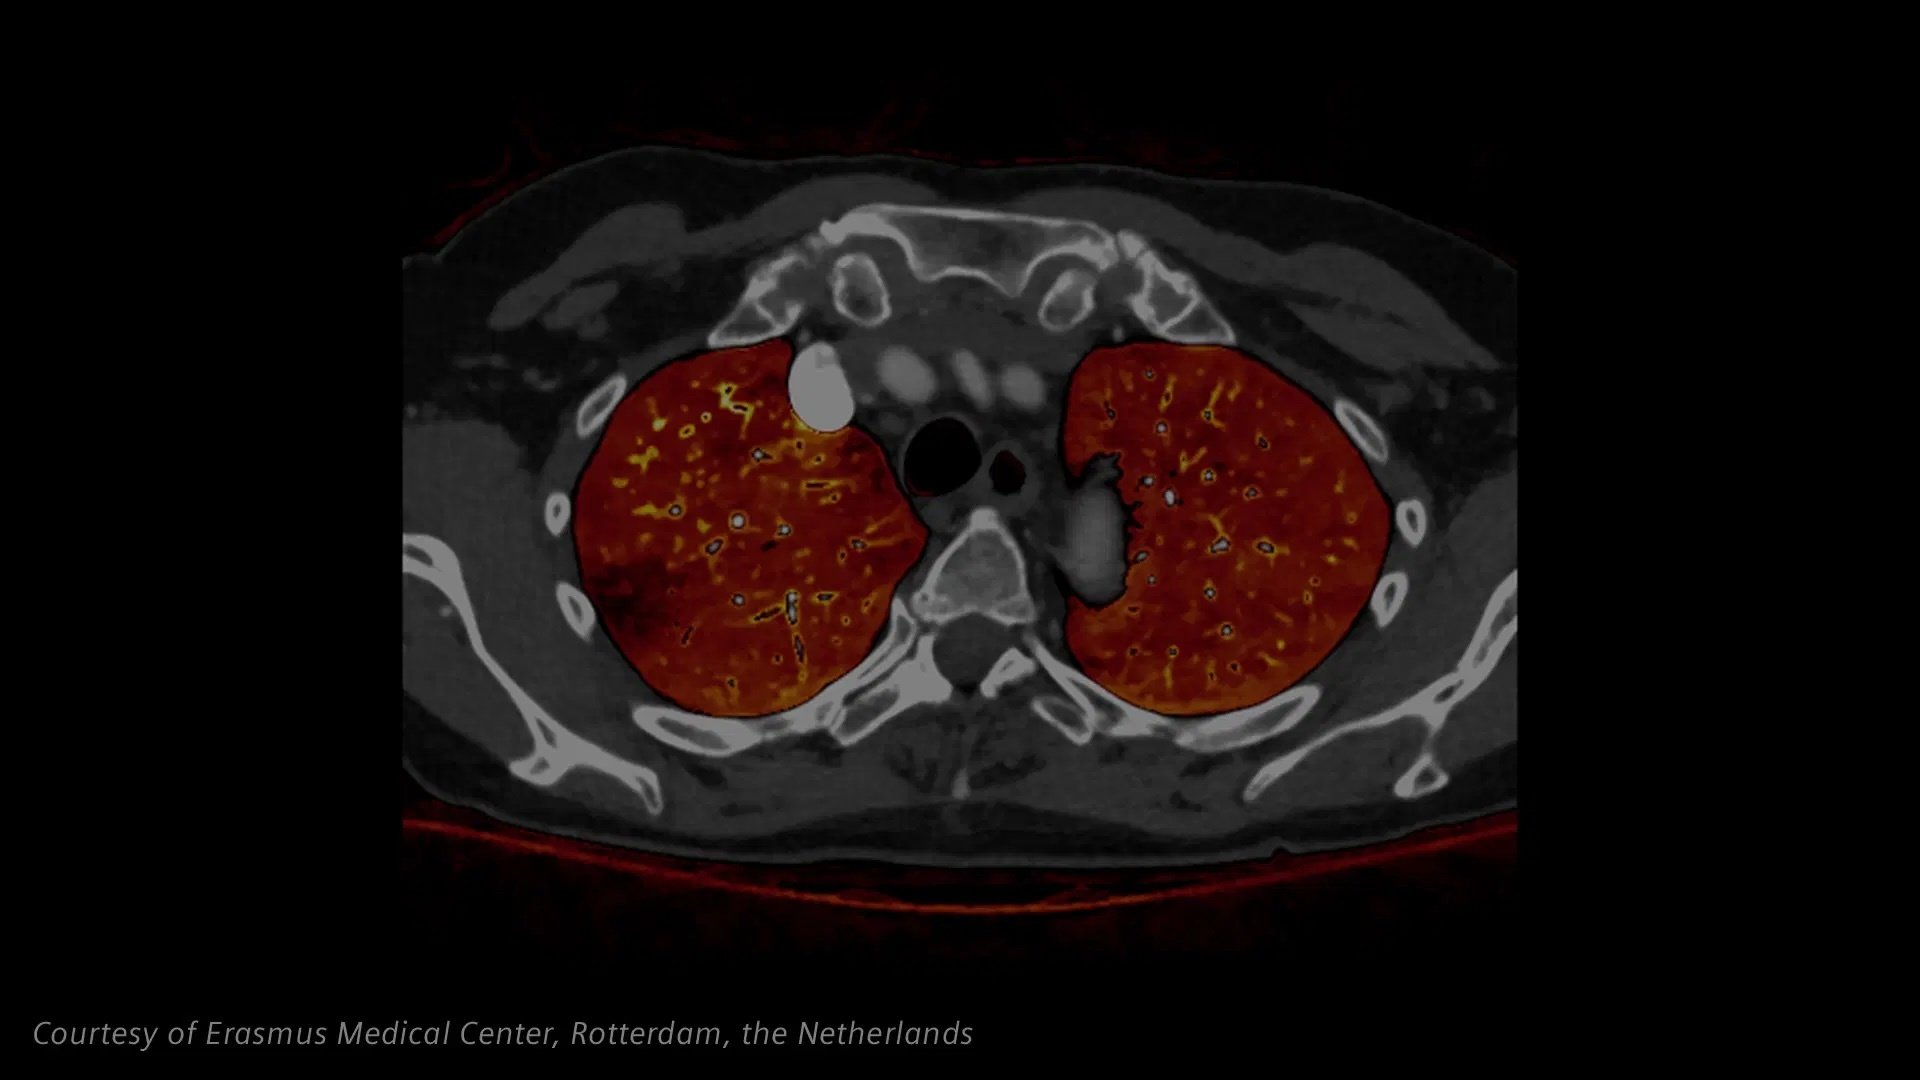

The Dual Source speed of NAEOTOM Alpha.Pro enables short scan exposure times such that the thorax can be visualized without a breath hold. Quantum Spectral Imaging provides additional information in one single scan.

The NAEOTOM Alpha.Pro offers high-pitch scanning and spectral information at any scan speed, helping to ease the workflow and support diagnosis. Perfusion and iodine maps contribute to accurate diagnosis in oncology and stroke assessments.